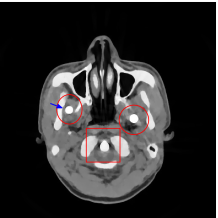

The proposed re-weighted JSR model requires a pre-estimation of the metal trace and weights in projection domain. They can be obtained fairly easily from a roughly reconstructed CT image using a simple reconstruction model. In this paper, we use the tight wavelet frame based analysis model [8]. This subsection describes the details on how metal trace and weights are computed using the NURBS-based cardiac-torso(NCAT) phantom [45]. Two metal components are implanted in the NCAT phantom as shown in Figure 1(a) and the simulated projection data is obtained from a multi-chromatic X-ray source. Details on the settings of the imaging system are postponed to Section 4.1.1.

The optimization problem (2.12) can be solved by the split Bregman algorithm [29, 8] efficiently, which is also equivalent to the alternating direction method of multipliers (ADMM) [24, 26, 28]. The reconstructed phantom image by model (2.12), denoted by , is shown in Figure 1(b). Metal location in image domain can be robustly estimated by the summation of the high frequency wavelet frame coefficients (Figure 1(c)) followed by a simple thresholding. Then, the index of the metal trace in Radon domain, denoted by , can be identified by the projection of the indicator function associated to the metal location (Figure 1(d)).

The NCAT phantom (shown in Figure 1(a)) and the cerebral phantom111http://see.xidian.edu.cn/vipsl/database_CTMR.html (shown in Figure 8(a)) are chosen as image phantoms. For the NCAT phantom, it has pixels. Two metal components (Titanium) are implanted in the image, which is shown in Figure 1(a) with red curves labeling the locations of the metals. For the cerebral phantom, it has pixels and three metal components (Titanium) are implanted. Both of the phantoms contain three major components, i.e. soft tissue, bone and metal components, and their linear attenuation coefficients can be found in [30].

Figure 7(a) shows that the reconstructed NCAT phantom from FBP has severe metal artifacts and is noisy. The reconstructed image from the unweighted JSR model (3.2) shown in Figure 7(b) has a better visual effect with noticeably less noise and metal artifacts. Sharp edges are also well preserved except for the blurry effects in the region surrounding the metals. The reconstructed image from NMAR shown in Figure 7(c) also has most of the metal artifacts suppressed and the regions surrounding the metals are much less blurry than the unweighted JSR. However, the unweighted JSR does a better job than NMAR in suppressing noise and preserving sharp image features away from the metals. TV-FADM is able to reconstruct images with minimum metal artifacts and noise, as shown in Figure 7(d). However, the metal components are fused with nearby structures which is highlighted by the red arrow. The reconstructed image from proposed re-weighted JSR model has the best overall quality with rather minor metal artifacts.

Figure 8 shows the reconstructed cerebral phantom from different methods. We highlight some regions with more distinct differences with red contours. Since the cerebral phantom contains more textures, it is more challenging than the NCAT phantom. The pros and cons of these methods are mostly the same as the previous example. However, we note that the reconstructed image from TV-FADM shown in Figure 8(e) has severe artifact, which is due to the well-known staircase artifact of TV regularization. We found that TV-FADM is relatively sensitive to the choice of its parameters. It is not easy to balance between sharpness of image features and metal artifacts reduction. The soft tissue around metal components is also not well preserved by the NMAR method as indicated by the blue arrow in Figure 8(d). Furthermore, the circled areas in Figure 8(d) show that there are still some artifacts around the metal. Same as the NCAT phantom, the proposed re-weighted JSR model has the best overall performance. Notice that the intensity of metals in Figure 8(d) and 8(f) seems lower than the rest of the reconstructed images. This is because we set the intensity of the metal components in the segmentation with the same mean value as that of bones. Increasing the value of metal components of can increase the intensity of metals in the reconstructed images, whereas it also introduces more artifacts around the metals.